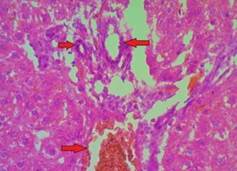

Fig. 5: G3 10X HandE stain. architecture of liver showing prominent microvesicular and macrovesicular fatty change

Fig. 6: G3 40X HandE stain architecture of liver showing prominent microvescicular andmacrovescicular fatty change

Fig. 1 and 2, G1 (Group 1) 10X and 40X HandE stain histopathology section of liver shown normal hepatic architecture compressed of hepatic lobules formed by the central vein and the cords of hepatocytes with indistinct sinusoidal dilatation in fig. 3,4,7and8. G2and4 (Group 2and4)10X and 40X HandE stain shown prominent sinusoidal dilatation.

Whereas G3 (Group 3)10X and 40X HandE stain histopathology shown lobular architecture of the liver with enlarged hepatocytes containing microvescicular and macrovesicular fatty changes with sinusoidal congestion.

We observed marked structural alteration, i.e. microvescicular and macrovesicular fatty changes in histopathology of liver of rats fed with high fat diet. Hyper lipidemic rats treated with ethanolic extract of Terminalia arjuna is shown normal architecture of liver histology. Ragavan, B., et al. reported in their study, high fat diet induced rat treated with Terminalia arjuna bark extract shown to partially reverse the damage (Fatty changes) [16].